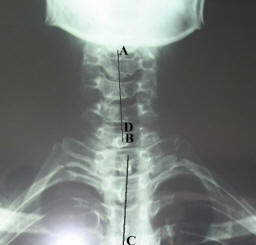

3.X線片可見上段胸椎側凸,頸6、7鏇轉,反向傾斜,椎曲變小或變直。

痊癒:疼痛消失,X線片示胸椎側凸,頸6、7椎鏇轉及傾斜恢復。

好轉:疼痛減輕,X線片示頸6、7椎鏇轉,傾斜改善。

無效:疼痛和X線片現實均無改善。